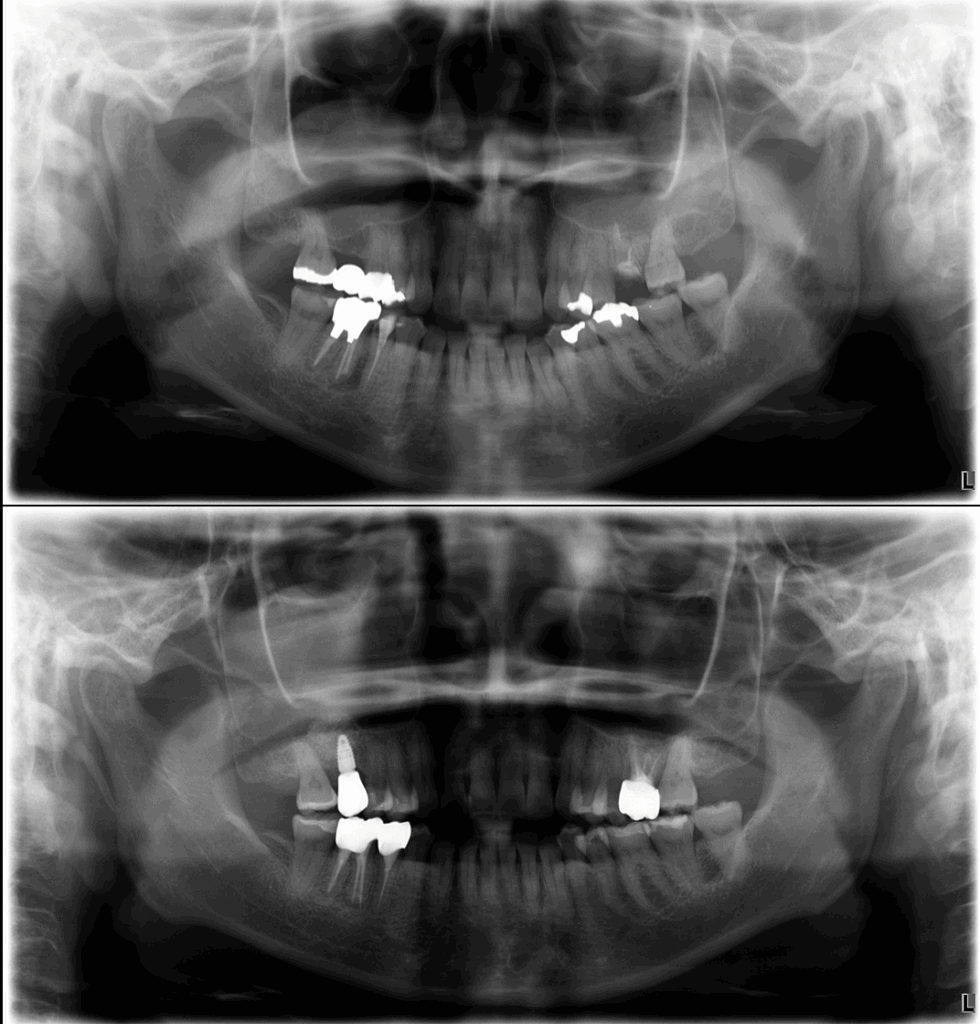

治療前

治療後

初診時の口腔内・レントゲンでは、以下の問題点が見られました。

- 二次カリエスによる大きな歯質欠損

- 残根に近いレベルまで崩壊

- 歯質の薄さから保持力がほぼ不可能

- 根尖に透過像(炎症の影)

- 噛むと痛い(咬合性の問題も併発)

- 被せ物が繰り返し脱離している既往

根管治療後には、根尖の透過像が明らかに改善し、炎症もコントロールされました。

治療終了後は以下の改善が得られました。

- 痛み・腫れの消失

- レントゲン上の透過像の縮小

- 歯肉が健康的なラインに安定

- セラミッククラウンが自然に適合

- 咬合が安定し、日常生活の痛みが消失

- 外科なしで歯を残すことに成功